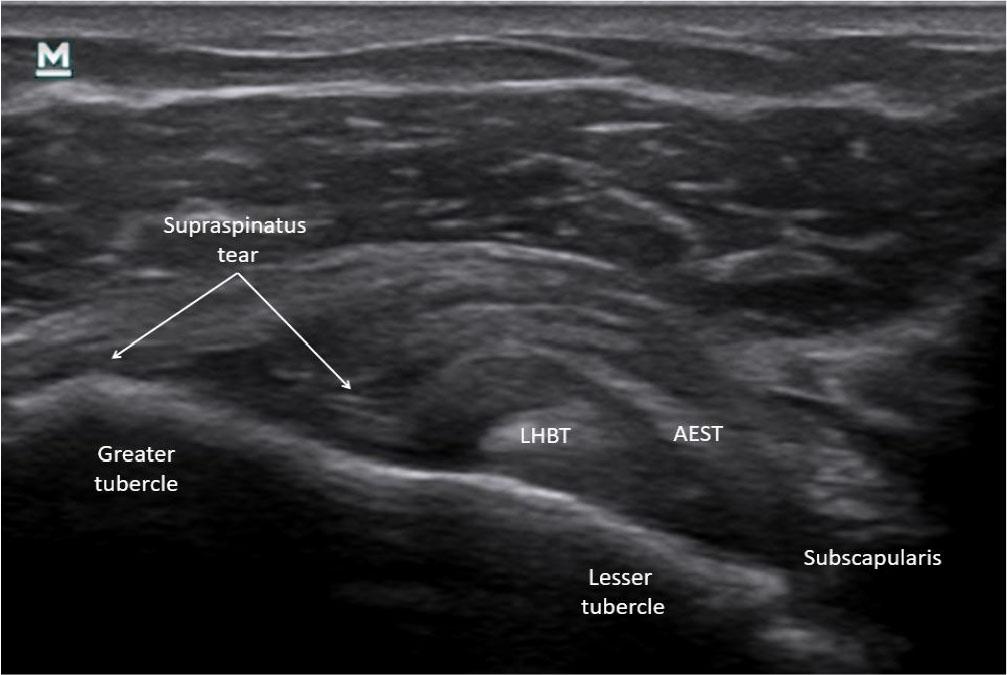

The most frequent subtype was Ia (6/19, 31.6%), with mild intrasubstance AEST tears (Fig. 9), occasionally with ganglion formation (Fig. 10). Subtype IIIa (4/19, 21.1%) involved complete supraspinatus tendon tears with retraction. Subtype IIb (3/19, 15.8%) included one mixed IIb+Ia case with a lateral tear plus intrasubstance lesion.

Mild intrasubstance tear of aponeurotic expansion of the supraspinatus tendon (AEST) at the base of the supraspinatus tendon in the right shoulder (AEST–supraspinatus classification: Ia, case 1)

Aponeurotic expansion of the supraspinatus tendon (AEST) subluxation medial to the long head of the biceps tendon (LHBT) with a full-thickness supraspinatus tear in the right shoulder (case 7)